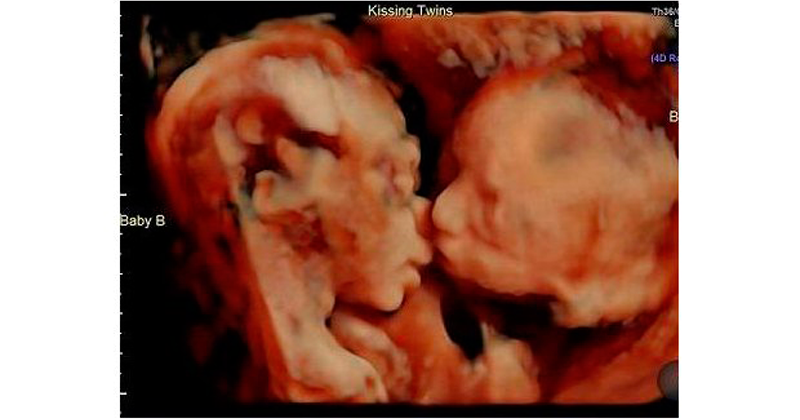

Gemelas se dan tierno beso en el vientre de su madre

La conexión entre hermanos es muy fuerte, incluso desde antes de nacer